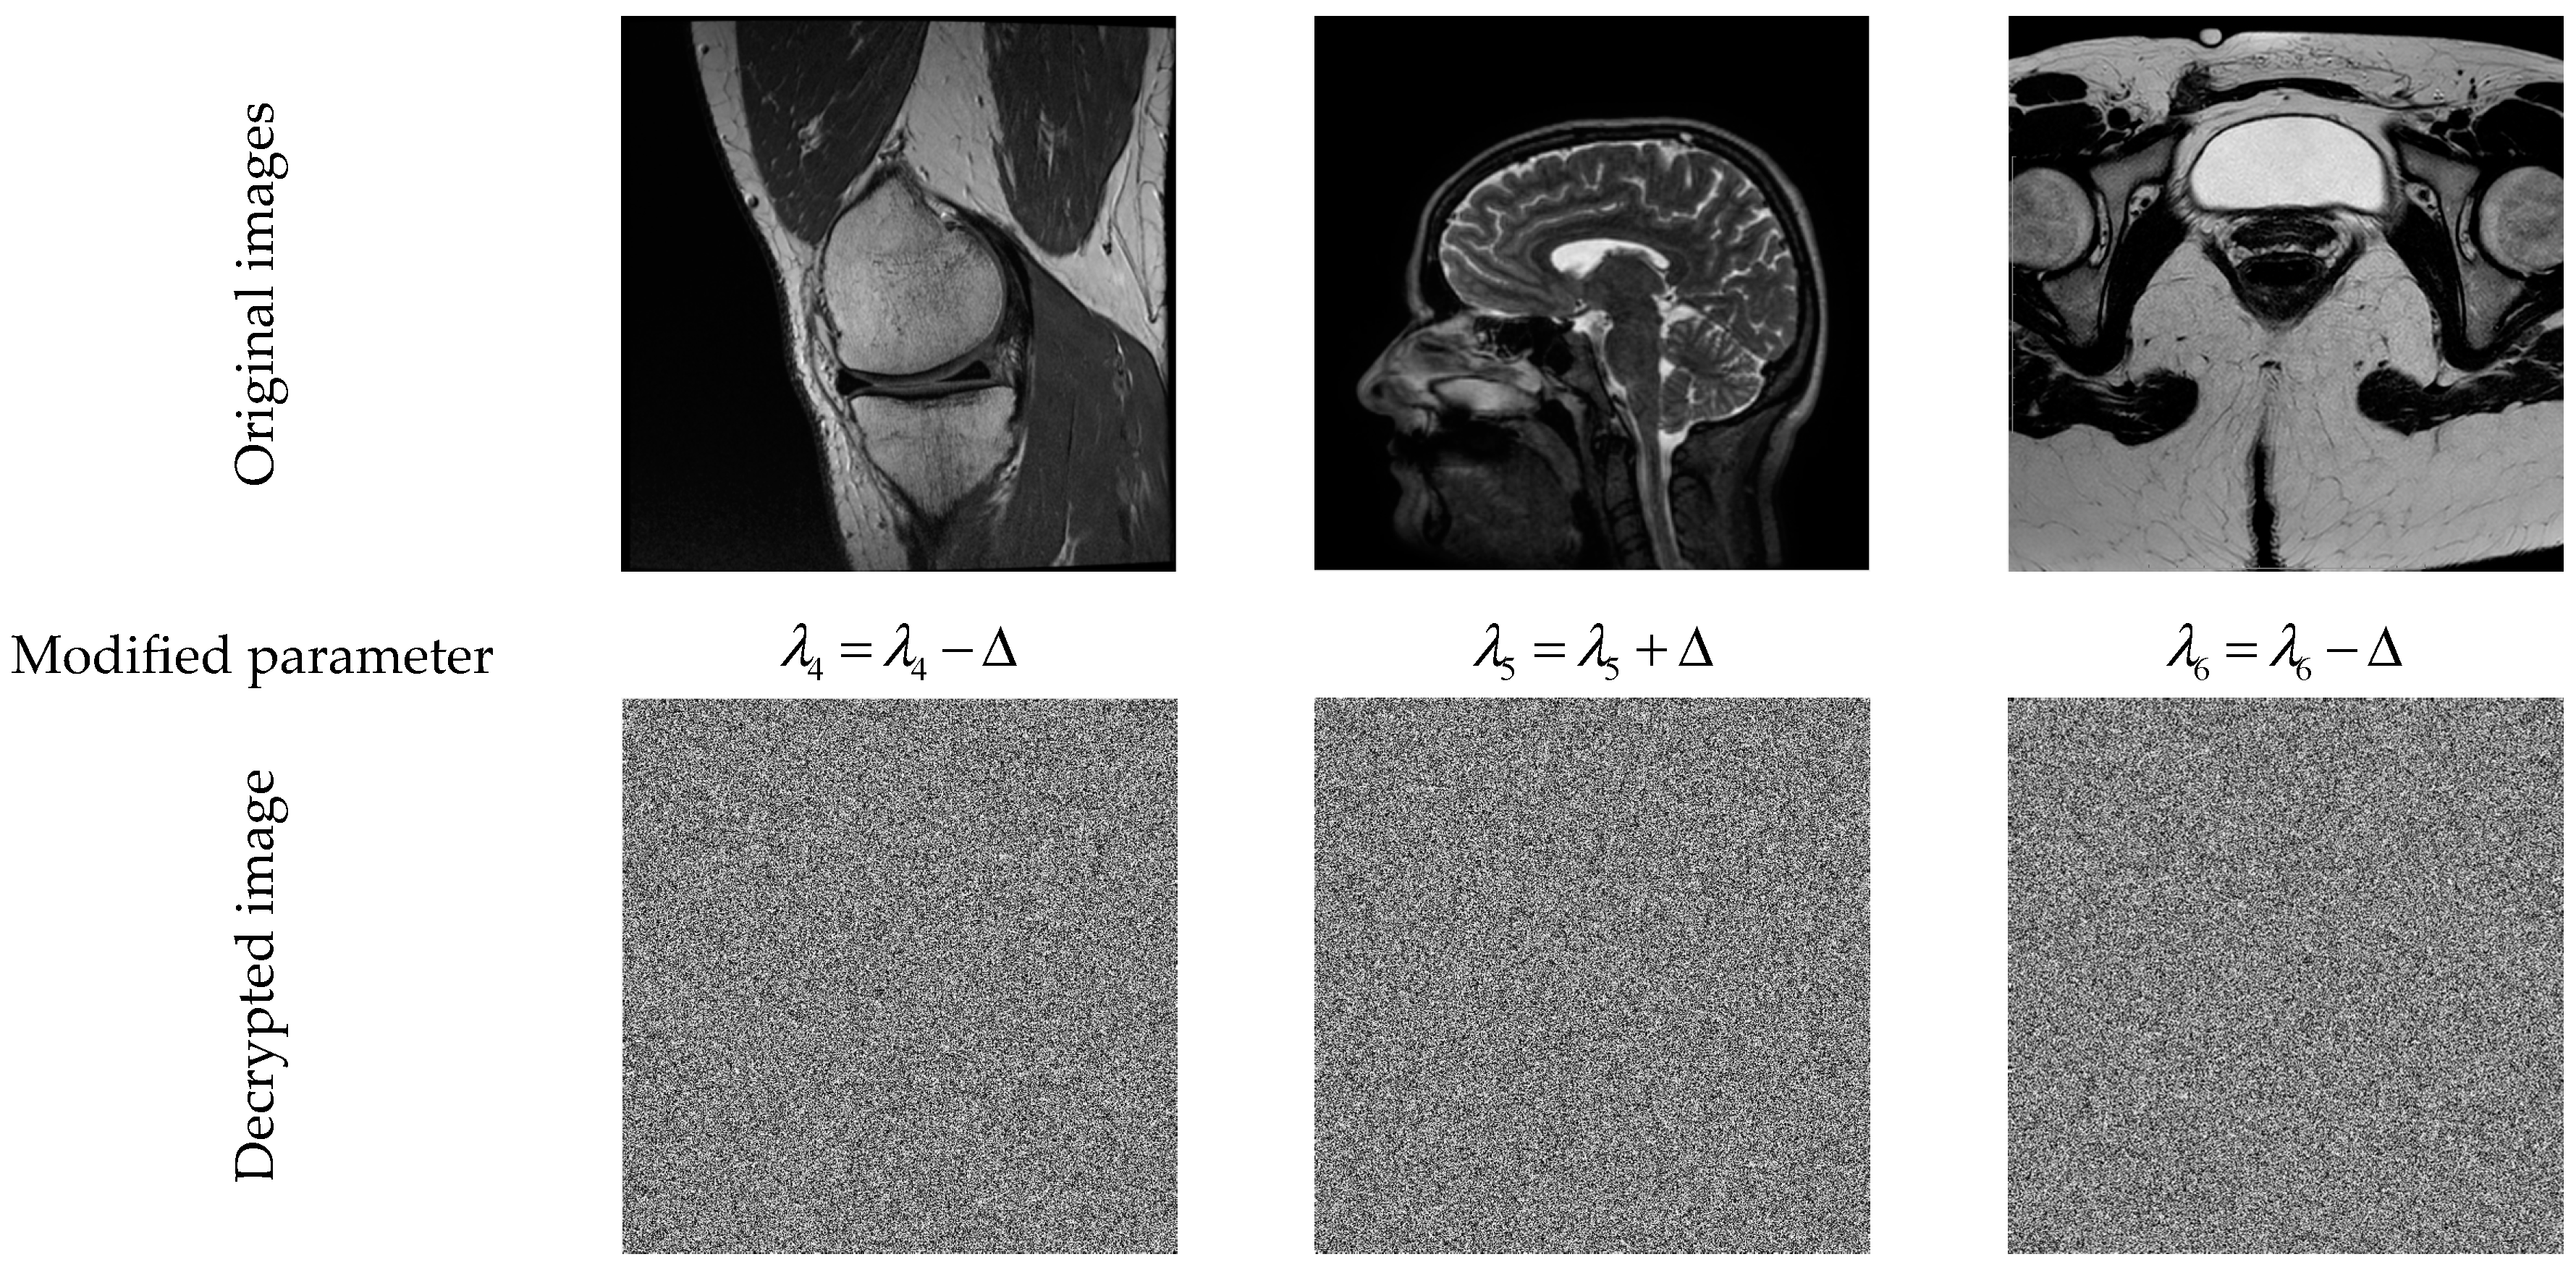

5.1. Sensitivity Analysis of the Secret Keys

- Define a security KEY to encrypt the first image in a dataset.

- (ii).

- Choose one (or more) parameter(s) of the KEY, and then increment the selected parameter by a small constant value (e.g., ) to generate a new security key (KEY*) that is used to encrypt the next image in the dataset, and so on. This strategy creates dynamic security keys, which prevents conventional attacks. For more information regarding this strategy, the reader is referred to [14,85].